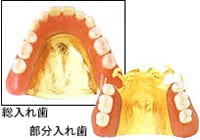

さまざまな入れ歯の種類 VARIOUS DENTURES

さまざまな症例に対応できるよう、目立たず美しく、吸着力とフィット感に優れ、きちんと噛むことができる入れ歯を多数取り扱っています。患者様の症状やライフスタイルに応じて選べますので、快適にお使いいただけます。